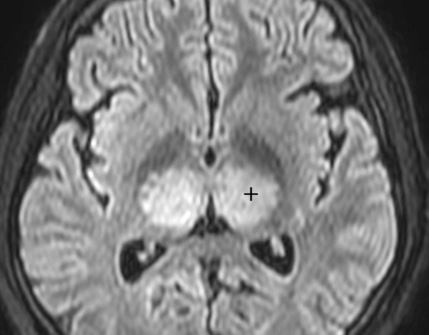

Encéphalite à Tiques (MEVE)

- Flavivirus (Vaccination recommandée)

- Progresse en suisse romande

- Syndrome grippal → pause → Déficits Neuro + Méningite

- Anomalies T2 des noyaux de la base